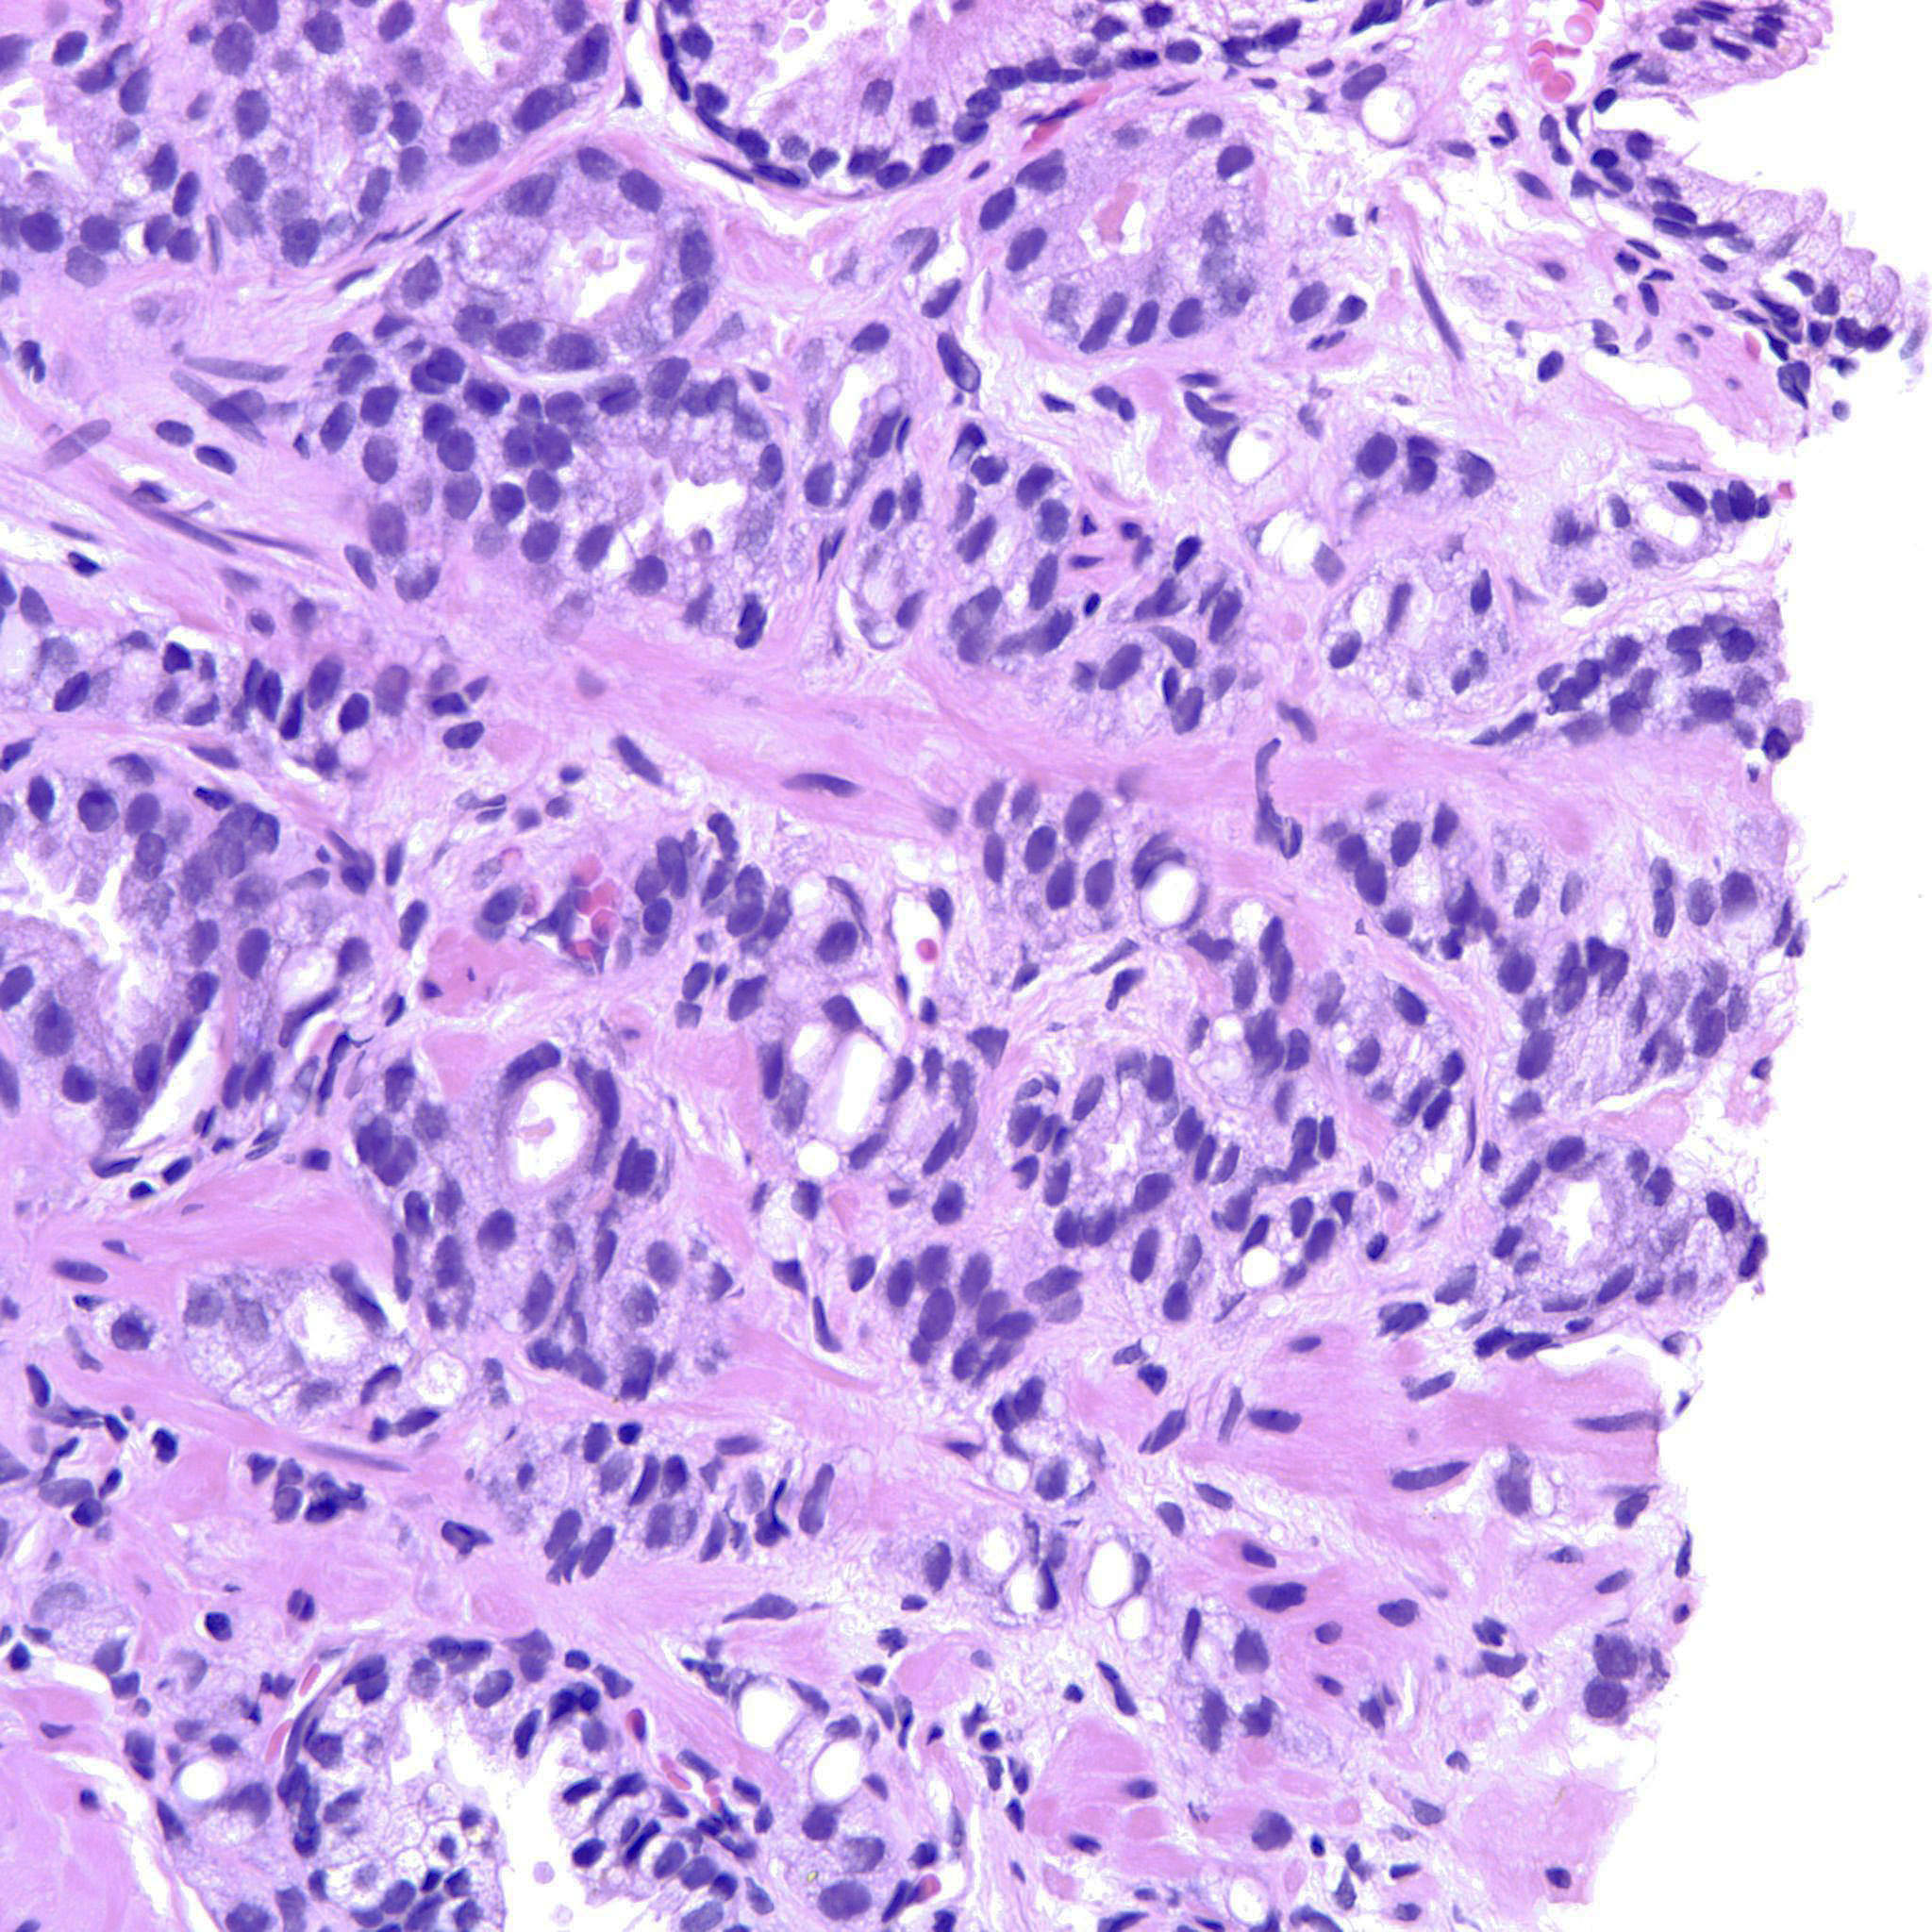

Prostate cancer grading

Case ID: 760